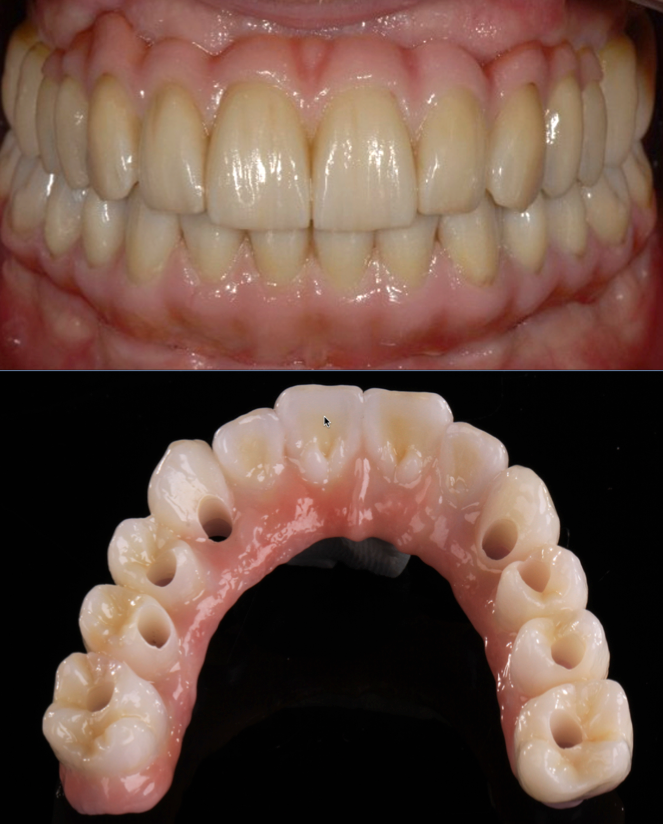

Fixed implant supported zirconium bridge

Often a fixed bridge is placed on four implants; this is often called an “All on Four”. In practice we would recommend that six implants will provide a better platform than four implants.

If at a later date you were to have a problem with a six implant supported bridge (which would be less likely than with a four implant bridge), you will still have five implants which is adequate support to continue. If you have a four unit bridge and lost one implant, the remaining three would be insufficient to carry the load and the bridge would fail.